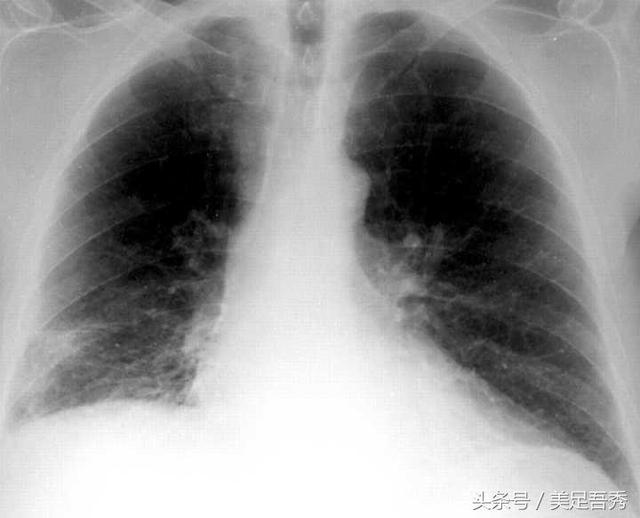

2.肺炭疽一般起病比较急,先前会有2-4天的不适,如寒战、高热等严重的中毒症状,咳嗽、血痰、呼吸困难等;肺部有啰音及胸腔积液。也可先出现低热、肌痛、干咳、心前区压迫(痛)感等,然后突然出现呼吸窘迫、气急、喘鸣、血样痰、咳嗽、胸痛、大汗等,伴寒战、高热、心率增快等。